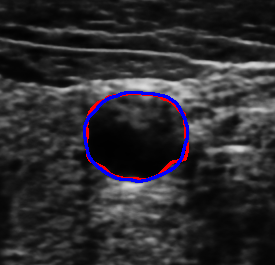

4.7 Downstream Task on Ultrasound Image Segmentation

To showcase the potential of the proposed denoising method quantitatively for ultrasound image understanding, we evaluate its impact on carotid ultrasound segmentation as a downstream task [9]. In this task, we use unseen noisy carotid images collected from the Clarius device. Then, unsupervised Segment Anything 2 (SAM2) [66] and the rule-based Flood Fill algorithm are used to extract the carotid artery from noisy and denoised images processed by various despeckling algorithms. In both cases, we place the seed point at the geometric center of the carotid lumen in each frame.

The quantitative result in terms of both IoU and AUC has been summarized in Table 6. To provide an intuitive visualization of the comparison, the results of SAM2 on a representative image and its denoised variants are presented in Fig. 12. It can be seen from Table 6 that the overall results using SAM2 are significantly improved in comparison to the Folld fill algorithm. This is primarily because of the strong generalization capability of the foundation model itself. Although the results produced by SAM2 across different images are comparable, the outcomes on images denoised by our method consistently demonstrate superior performance. The AUC reaches the highest score among all methods, while the IoU achieves the second-best performance. This performance advantage becomes more pronounced when using traditional region-growing algorithms such as the Flood Fill method. Significant improvements in both AUC ( vs ) and IoU ( vs ) are observed when applying the proposed Speckle2Self denoising approach.